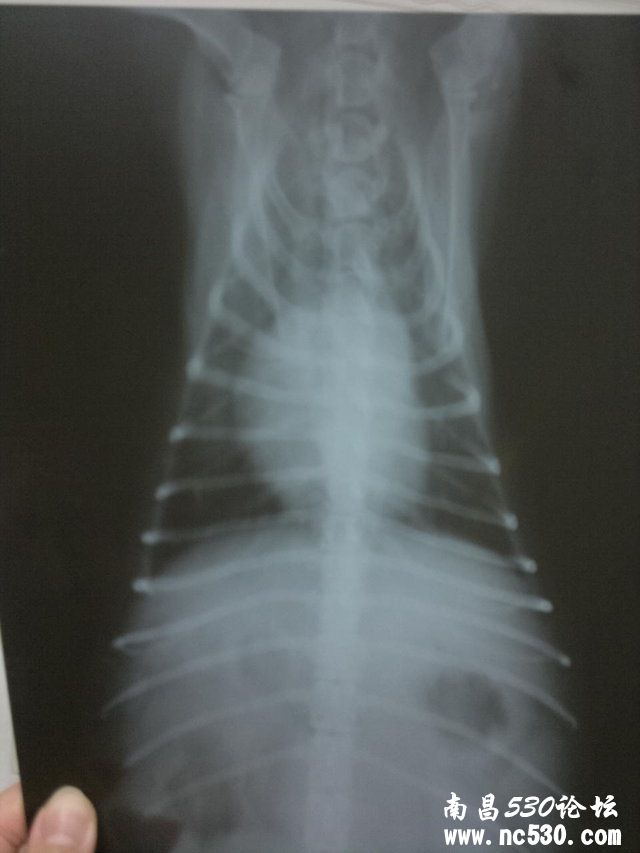

排便如何:正常,一天最少二回,形状颜色都很好 症状:大概有一个月了,没精神总爱趴着,有时呼吸间身体有轻微拌动,睡觉有时会喘几下,溜弯时不爱走近几天不爱吃饭. 12月18日在家附近的宠物诊所诊断说心肌肥大,第二天发现外阴流脓水诊断子宫蓄脓,后有医生说开放型的叫子宫内膜炎,现在打消炎针.  以下是12月18日的胸片

12月20日在一家医院输液,第一天效果挺好回家主动吃饭第二天就没精神了第三天刚打第一组能量就不行了浑身发抖医院马上打了强心剂,马上就不打了. 12月23日到我们这的农业大学动物医院,医生说它这种情况不能输液开了三针拜有利(每天0.5ML)12月26日恢复的特别好又补打了一针拜有利,医生说不用去了就是注意下次发情期就行了.

12月29日晚10点左右又出现舔外阴,大口喘气的情况,12月30日早10点多发现外阴有少量浓液流出,不吃饭不让人触摸下半身有发脾气的迹象.马上带去农大动物医院,14:00多打一针拜有利,一针缩宫素,头包点滴至17:00期间很安稳无异常是(就是没精神)外阴持续流出非常浓稠液体. 12月30日14:00测直肠内温39.5度 12月30日晚上吃了些饭(食欲可以) 12月31日10:00去医院复查没精神,下车后后腿无力有点支撑不住身体.10:00多打一针拜有利(0.4ML)医生诊断贫血,开补血口服液.回家后12:30分左右给狗服用12ML补血口服液.13:30左右吐了一回黄色的液体的水.估计是补血口服液.14:00喂了40ML婴儿米粉糊.之后不久开始大口喘气(注:今天一直不间断的大口喘气)14:29分又给服8ML补血口服液(至发贴没有吐出来)现在一直在喘,并且后腿无法支撑身体.(打点滴都是打在前腿上的) 好心医生给看是我家宝贝到底是怎么了.在线等救命!!!!!!